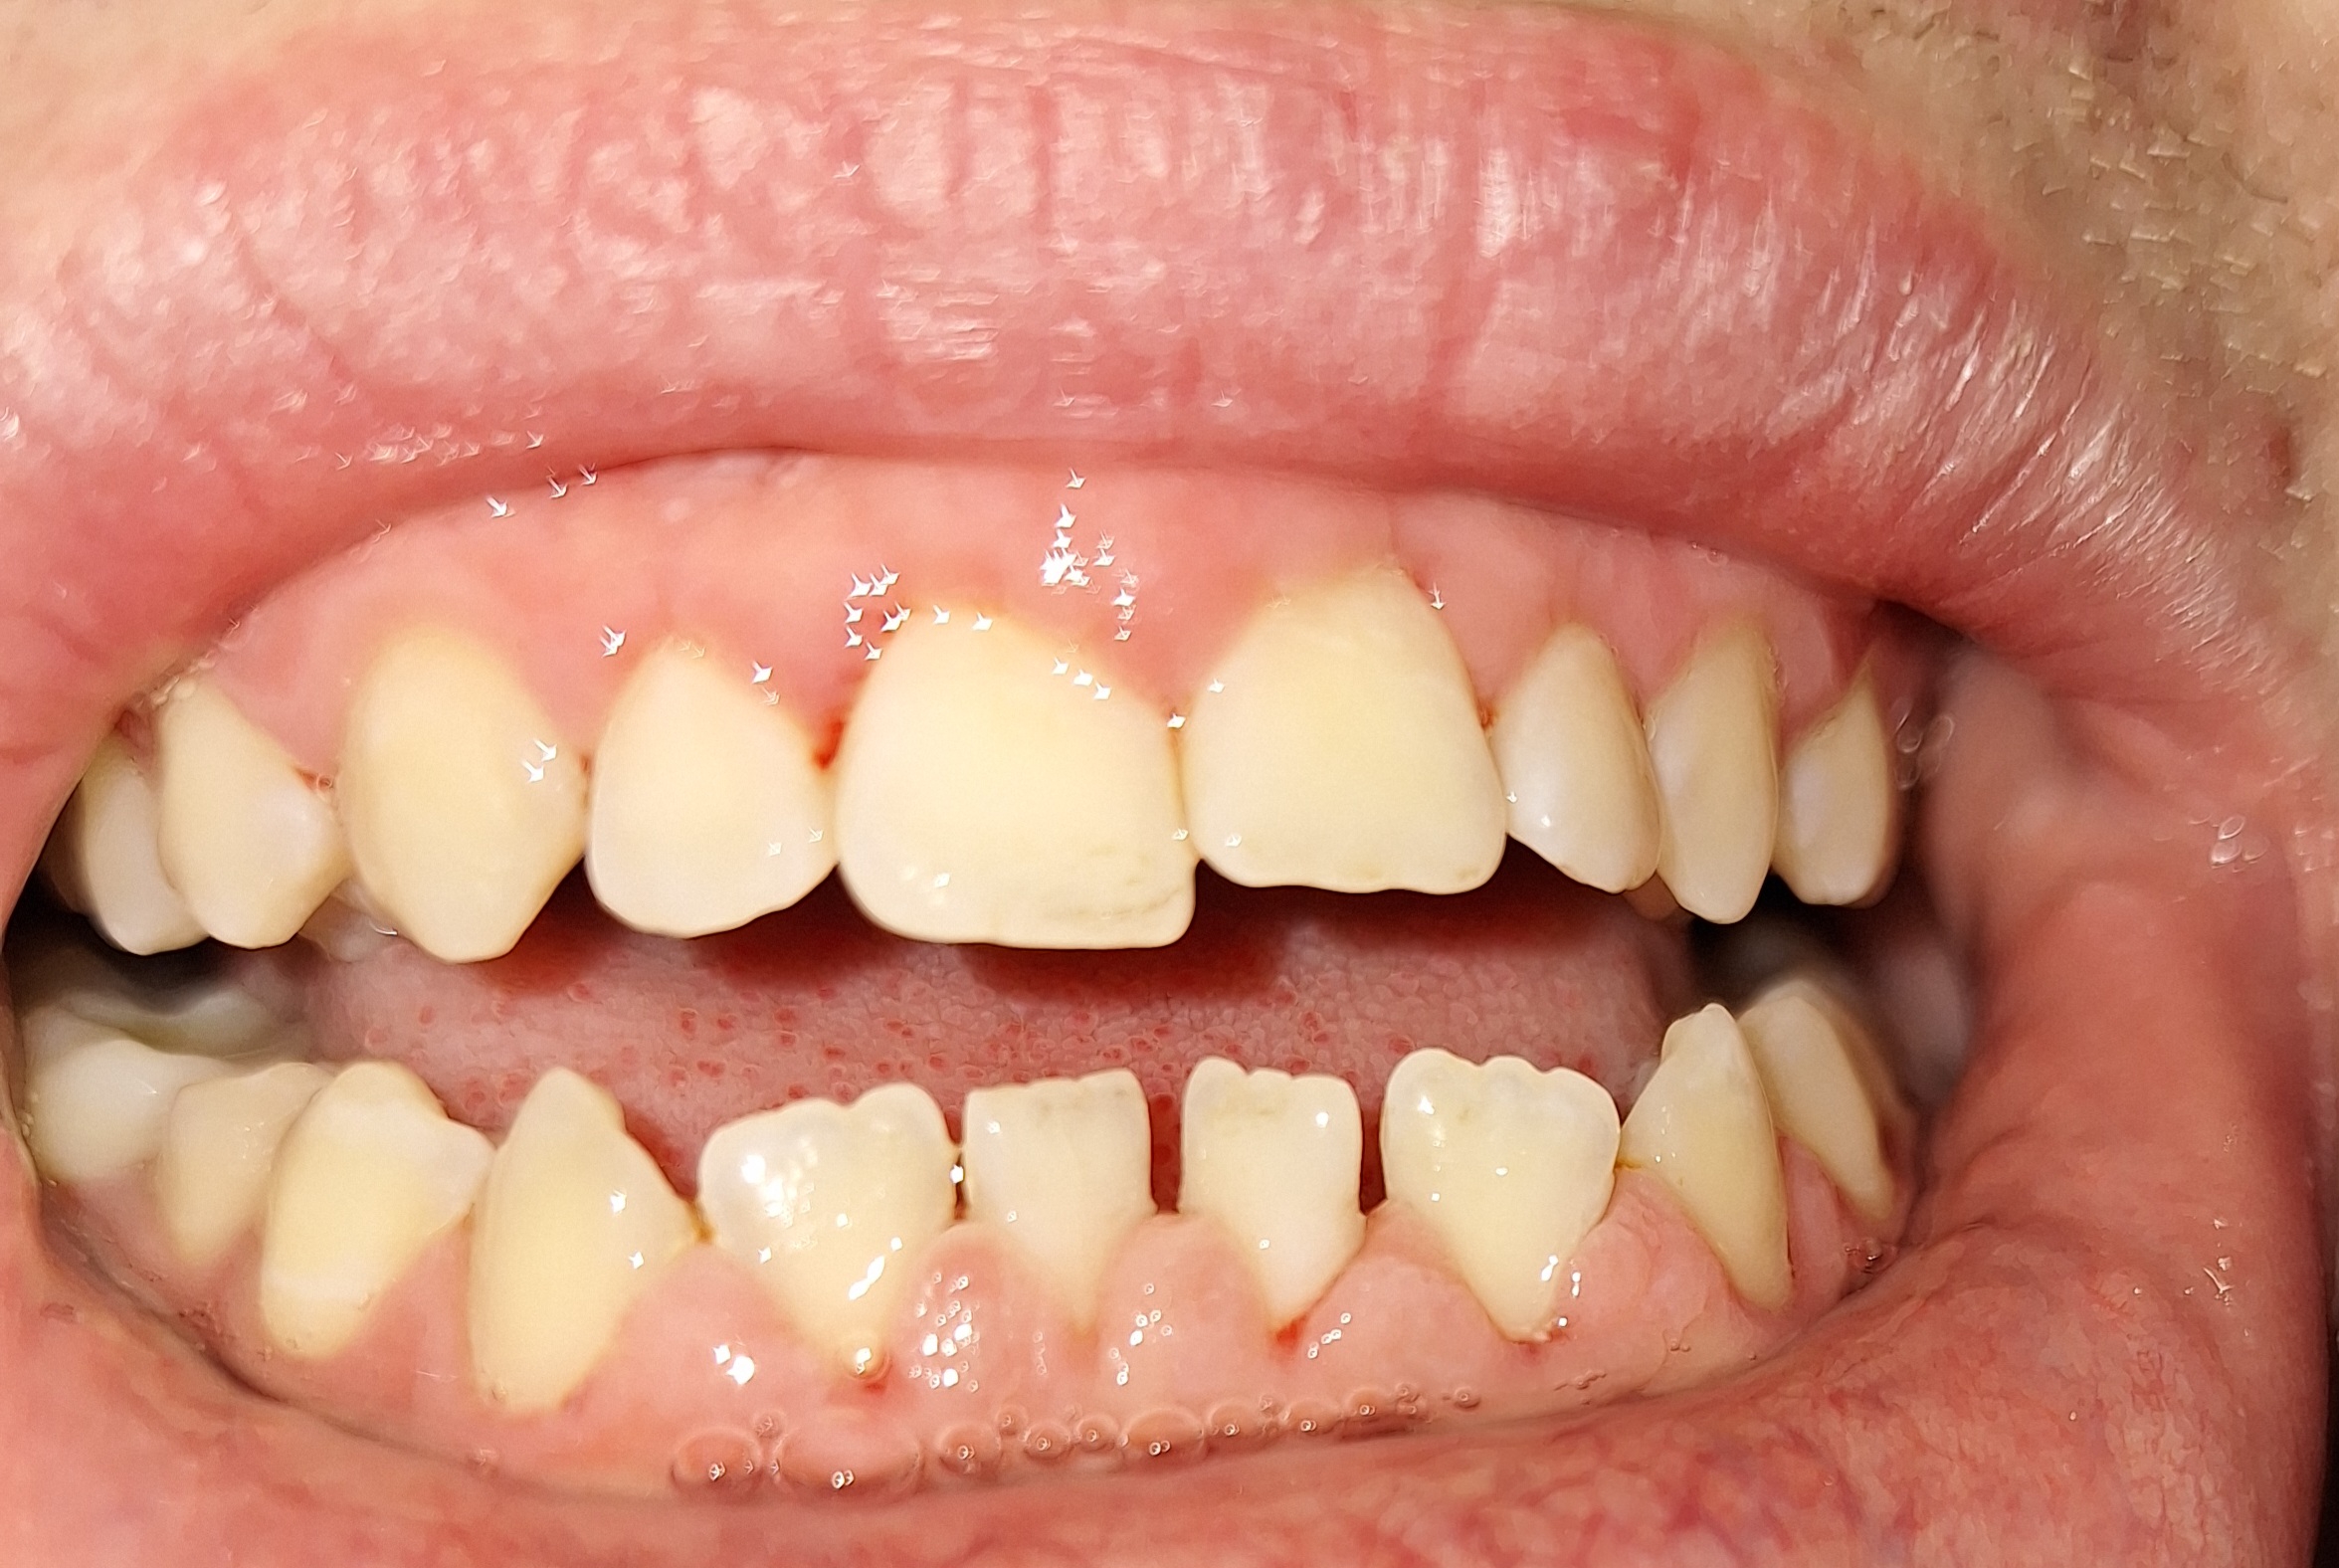

Опустились дёсны в нескольких местах, обнажились шейки зубов. Чувствительные, болят от прикосновений, могут реагировать на холодное, горячее, сладкое.

Ситуация как примерно на пик2.